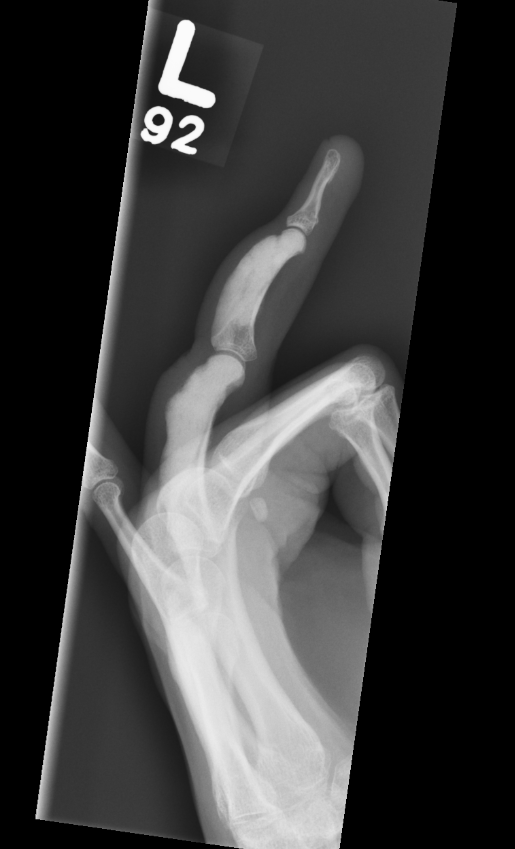

X-ray

Sclerotic lesions of bones

- undulating cortical hyperostosis

- look like wax dripping down the side of a candle